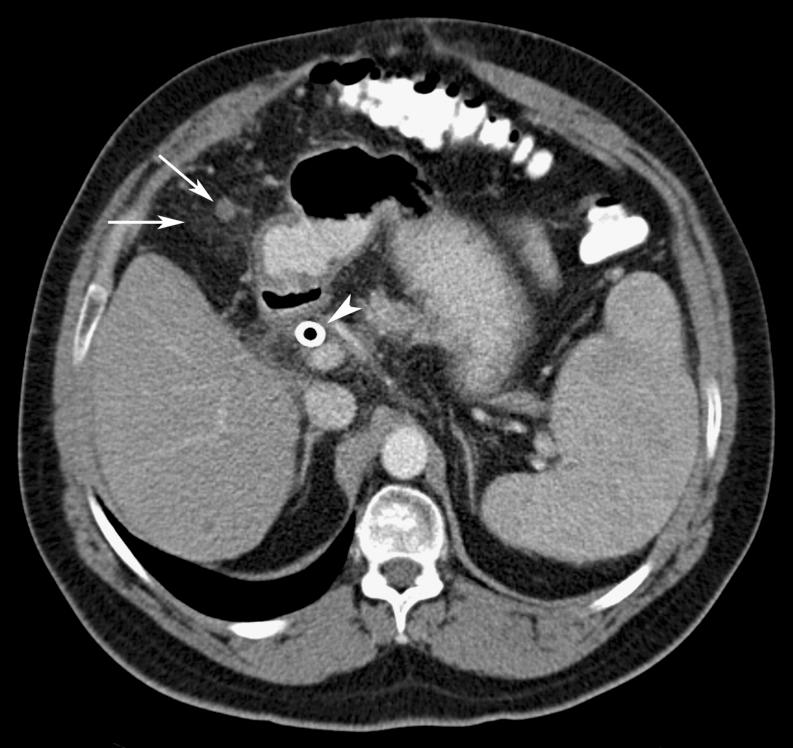

Omental cakes typically are associated with ovarian carcinoma, as this is the most common malignant aetiology. Nonetheless, numerous other neoplasms, as well as infectious and benign processes, can produce omental cakes. METHODS: A broader knowledge of the various causes of omental cakes is valuable diagnostically and to direct appropriate clinical management. RESULTS: We present a spectrum of both common and unusual aetiologies that demonstrate the variable computed tomographic appearances of omental cakes. CONCLUSION: The anatomy and embryology are discussed, as well as the importance of biopsy when the aetiology of omental cakes is uncertain.